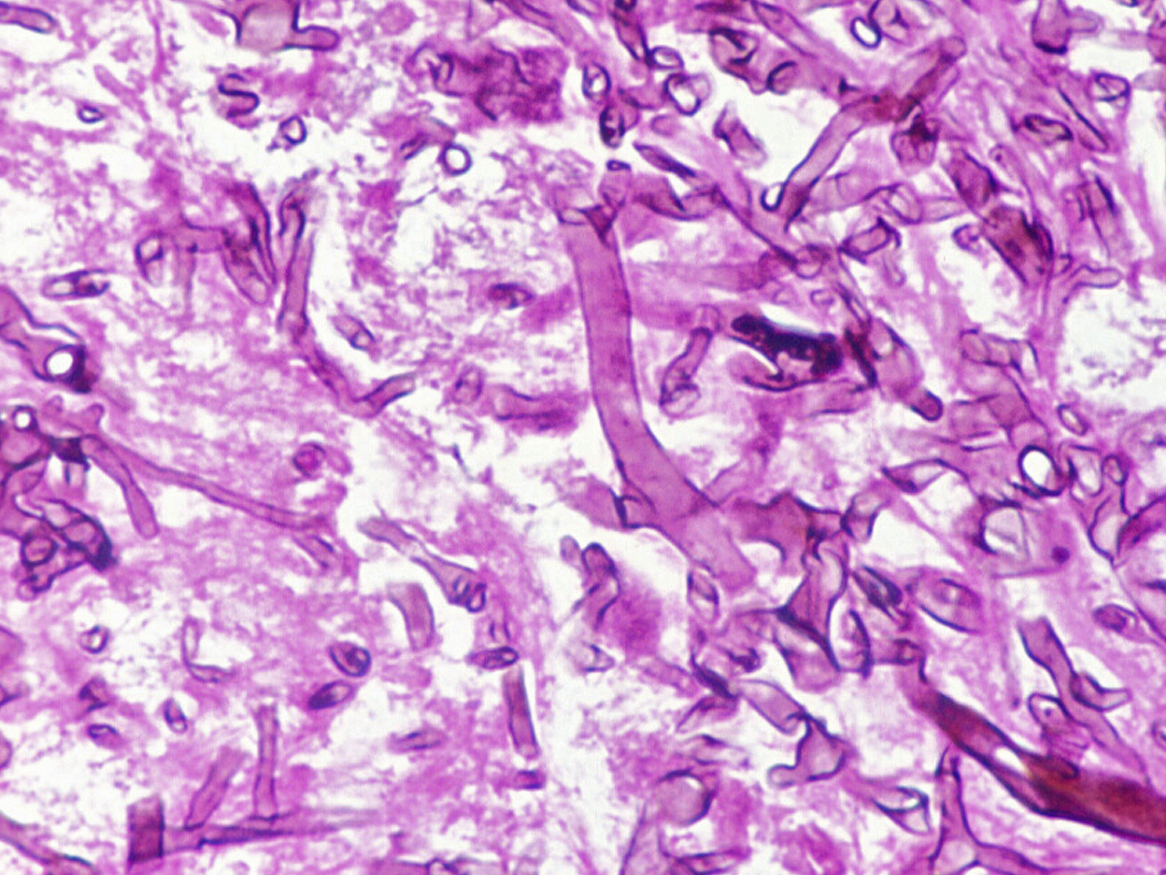

Lobomycosis histology

GMS stained tissue specimen showing numerous darkly pigmented yeast-like cells, often in chains, 9-12 um in size.

Direct microscopy:

(a) Tissue can be macerated and mounted in 10% KOH and Parker ink or calcofluor white mounts or (b) Tissue sections should be stained using PAS digest, Grocott's methenamine silver (GMS) or Gram stains.

Interpretation:

The presence of chains of darkly pigmented, spheroidal, yeast-like organisms tentatively referred to as Loboa loboi is typical for lobomycosis.